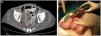

El paciente presentó, al 4.° día postoperatorio, un cuadro de obstrucción intestinal, evidenciándose en la TC abdominal urgente una masa obstructiva y perforada a nivel de íleon (fig. 1A), indicándose cirugía urgente donde se evidenció peritonitis localizada en FID e invaginación intestinal causada por una masa necrosada y perforada de 12cm localizada en íleon terminal (fig. 1B). Además, se encontraron numerosas adenopatías reactivas en meso adyacente, precisando lavado de la cavidad abdominal, resección de la tumoración y anastomosis íleo-ileal para reconstrucción del tránsito. La evolución postoperatoria cursó sin incidencias siendo dado de alta el 7.° día del postoperatorio. El análisis histopatológico de la tumoración abdominal confirmó el diagnóstico de metástasis de carcinoma pleomórfico pulmonar de 12cm (pT2bN0M1b).